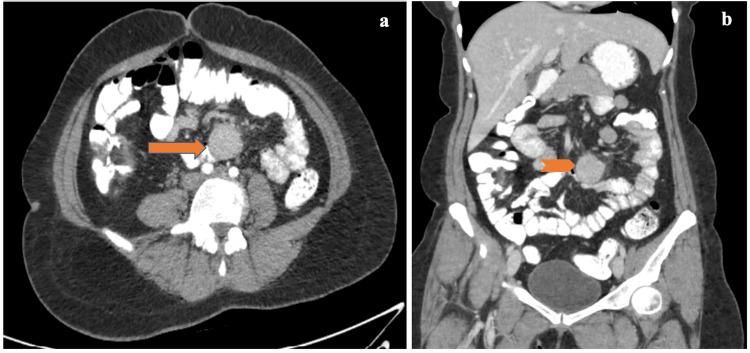

Castleman disease (CD) is a benign lymphoproliferative disorder of unknown etiology, which can involve any part of the body. CD can involve a single lymph node (unicentric) or multiple lymph nodes (multicentric) of which unicentric CD is the most common type. The unicentric CD is usually localized, asymptomatic, and often appears as an incidental mass on radiographs, whereas multicentric CD is characterized by systemic involvement. Mesenteric involvement of CD is very rare. In this article, we present a case of the unicentric CD of small bowel mesentery, which mimicked a neuroendocrine tumor preoperatively.

Castleman病(CD)是一种病因不明的良性淋巴增生性疾病,可累及身体的任何部位。CD可累及单个淋巴结(单中心型)或多个淋巴结(多中心型),其中单中心型CD最为常见。单中心型CD通常局限、无症状,在X线片上常表现为偶然发现的肿块,而多中心型CD的特点是全身受累。CD累及肠系膜非常罕见。在本文中,我们报告一例小肠系膜单中心型CD病例,该病例术前误诊为神经内分泌肿瘤。